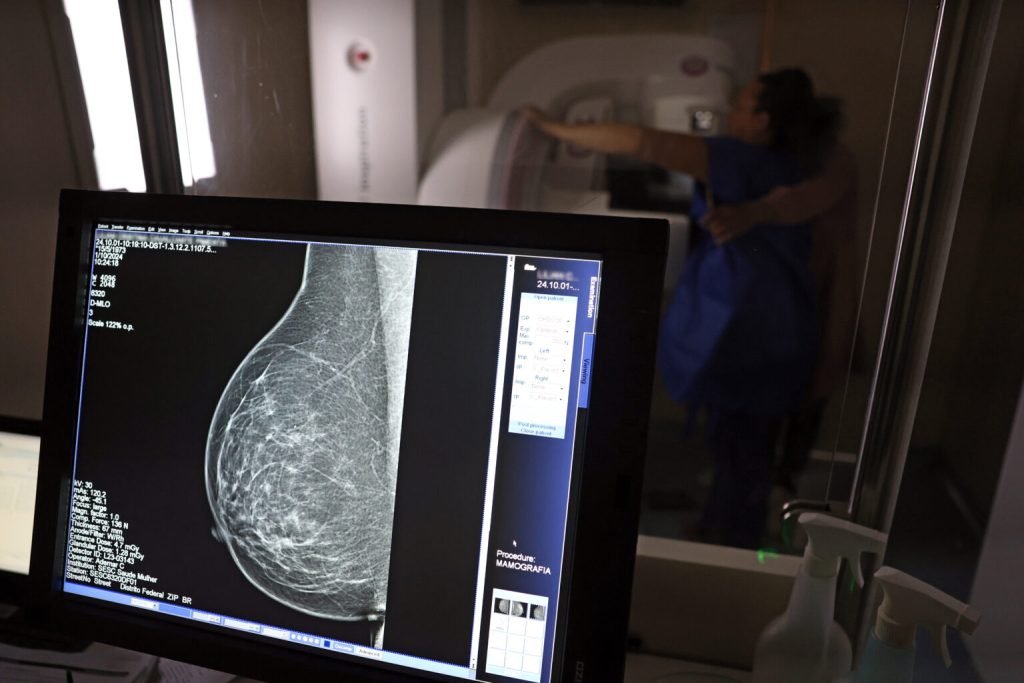

Durante todo este mês, como parte da campanha Outubro Rosa, o Instituto de Assistência à Saúde dos Servidores Públicos do Estado do Piauí (Iaspi) vai liberar a coparticipação nos exames de mamografia, realizados através do Iaspi Saúde.

A segurada fica isenta da coparticipação de 10% sobre o valor do exame durante todo o mês, como incentivo à realização da mamografia, exame que ajuda a identificar um tumor logo no início, e é indispensável para o rastreamento em mulheres acima dos 40 anos.

A diretora reforça também que, mais importante que o autoexame da mama, é a mamografia, pois detecta o tumor ainda em seus estágios iniciais, aumentando sobremaneira a chance de cura.

Há evidências que apontam 95% de chance de cura em casos, em que o câncer de mama é diagnosticado em estágio inicial. Para auxiliar no diagnóstico precoce é essencial realizar os exames de rotina dentro dos intervalos recomendados pelo seu médico.